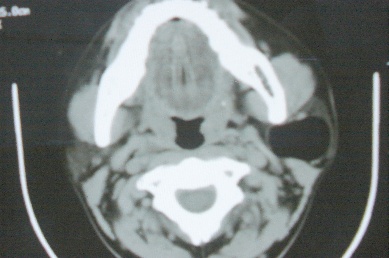

ct10755,男,28岁。发现左侧腮腺区肿块几年,今要求ct检查。左侧腮腺区低密度影,ct值-153hu。

左侧腮腺区囊状低密度影,ct值-153hu,考虑腮腺脂肪瘤。

病灶为一边界清晰脂性区,其内未见实质性组织.支持考虑:左侧腮腺脂肪瘤可能性大.

ct能定性的良性肿瘤不多,对脂肪瘤的诊断是比较有把握的,加大窗宽还可以看到里面有分隔

ct值-153hu,腮腺脂肪瘤。